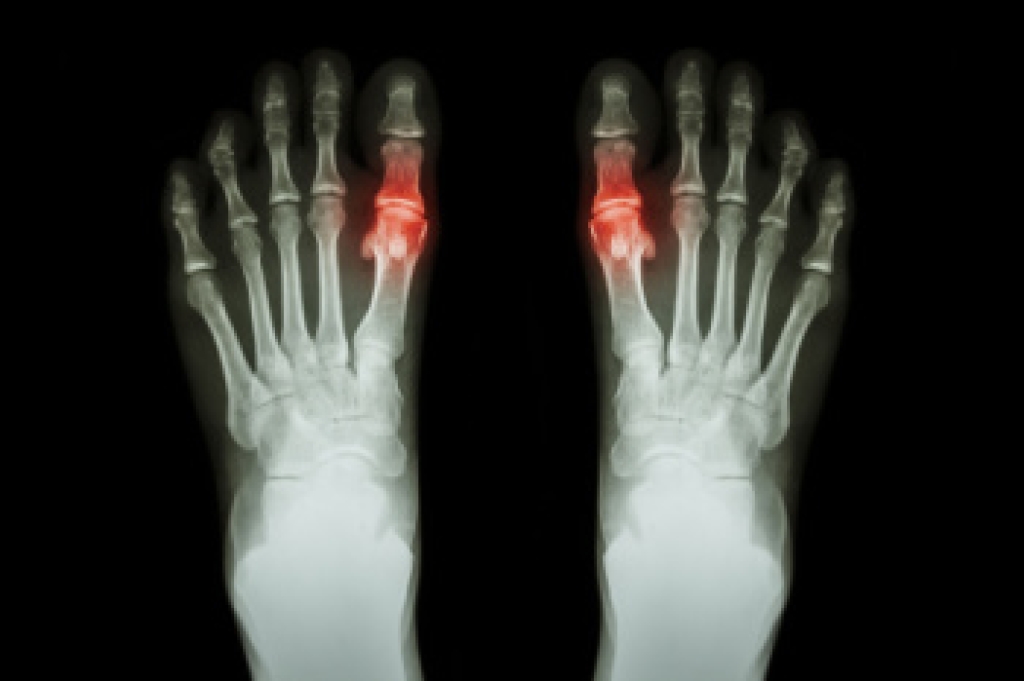

Gout is a form of arthritis that is characterized by sudden, severe attacks of pain, redness, and tenderness in the joints. The condition usually affects the joint at the base of the big toe. A gout attack can occur at any random time, such as the middle of the night while you are asleep.

- Intense Joint Pain - Usually around the large joint of your big toe, and it most severe within the first four to twelve hours

- Inflammation and Redness -Affected joints may become swollen, tender, warm and red